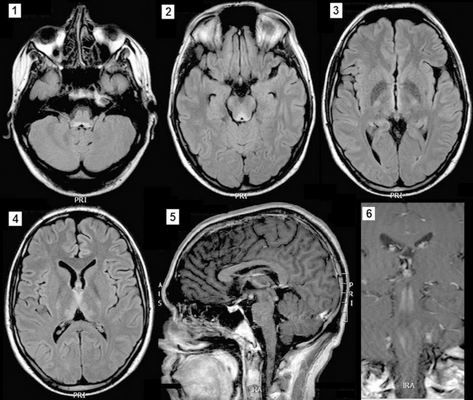

1 — гиперинтенсивный сигнал не только от периакведуктального серого вещества и маммилярных тел, но и белого вещества среднего мозга.

2, 3 — гиперинтенсивный сигнал от отдельных участков серого вещества коры головного мозга.

4 — участок центральной демиелинизации в области среднего мозга и верхней части варолиева моста.

5 — накопление контраста в оболочках мозга и отдельных участках коры [4].

Так, при МРТ головного мозга может выявляться поражение определенных участков серого вещества, в данном случае поражено серое вещество покрышки среднего мозга. Почти всегда при синдроме Вернике-Корсакова выявляется поражение мамиллярных тел, данный снимок не является исключением. На изображении также видно поражение гиппокампа и гипоталамуса с незначительным накоплением контраста в этих областях, также характерное для СВК.